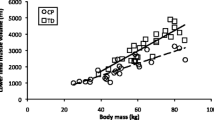

Physical characteristics of subjects in the BSCP and TD groups are summarised in Table 2. There were no group differences in age, body mass, height, or BMI (p > 0.05). The GMFCS level of the BSCP subjects are also presented in Table 2. The average standard deviation representing reproducibility of intramuscular fat averaged across all muscles was 0.33%.Figure 2 shows a histogram of group-averaged percentage IntraMF and IMAT. The BSCP group had a significantly higher average percentage IMAT (p < 0.001) and IntraMF compared to the TD group for all muscles investigated (p < 0.001), with the soleus having the largest percentage fat difference (12.9% greater in BSCP group). In the BSCP group, IntraMF was significantly correlated between all muscles measured (r = 0.697 to 0.947, p < 0.001 to p = 0.025) except for the soleus, which did not correlate with any other muscle (r = 0.437 to 0.587, p = 0.074 to 0.206). Figure 3 shows a histogram of group-averaged SF/M ratio. The mean SF/M ratio was 1.9 times greater in the BSCP group compared to the TD group; however, this difference was not statistically significant (p = 0.179). Example images for a case and age-matched control are given in Figure 4.

One-way ANOVA and post hoc analysis revealed significant differences in IntraMF levels by GMFCS level (p < 0.001), with GMFCS level III significantly higher compared to GMFCS levels I and II (p < 0.001 and p = 0.001 respectively). No significant difference was observed in IMAT or SF/M with GMFCS level (p = 0.131). In the TD group, SF/M was correlated with IMAT (r = 0.81, p = 0.005) but not with IntraMF (r = 0.182, p = 0.206), and no correlation was observed between IMAT and IntraMF (r = 0.251, p = 0.079). In the BSCP group, no correlations were observed between SF/M and IMAT (r = 0.392, p = 0.262) or IntraMF (r = 0.134, p = 0.353); IMAT and IntraMF were significantly correlated (r = 0.529, p < 0.001).

We conducted MRI measurements of IMAT, SF/M ratio, and IntraMF on 10 young adults with BSCP and 10 of their TD peers. This is the first study to show that ambulant adults with BSCP have raised levels of IntraMF, ranging from 2.3 to 34.4%. Percentage IntraMF was also found to be significantly different between GMFCS levels, with those at GMFCS III having greater fatty infiltration. These differences in IntraMF by GMFCS level suggest IntraMF maybe related to the degree of mobility impairment. This may be due to decreased physical activity with increasing mobility impairments.

Greater intramuscular fat may also be a marker of impaired mitochondrial content and/or function [44]. The increased intramuscular fat content observed in this study, particularly in the soleus, indicates that patients with cerebral palsy may have a greater risk of developing obesity related diseases, particularly type-II diabetes. Since IntraMF was observed to be greater with increasing GMFCS level, this risk of obesity-related disease may increase with decreasing functional ability. However, intramuscular fat is only one factor associated with the risk of developing obesity related diseases. Future studies of activity levels, fat levels, and glucose tolerance, are required to investigate the risk developing cardio-metabolic diseases in this patient group.